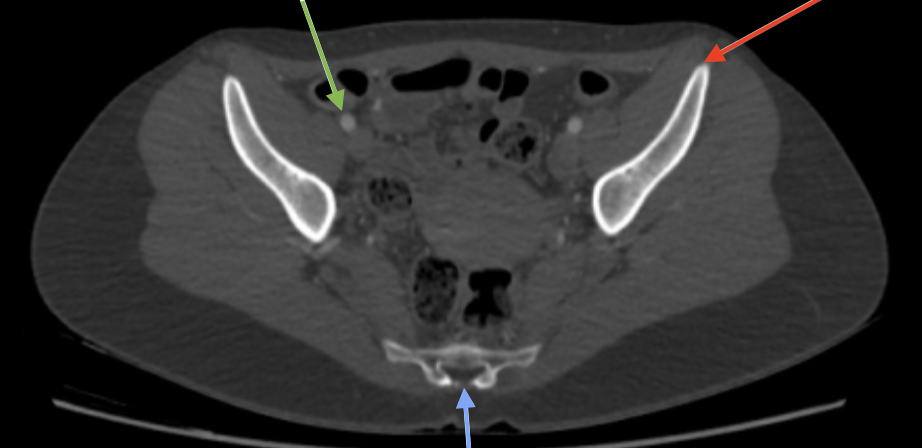

32

New cards

v iliaca communis dx

grön

33

a iliaca communis dx

orange

34

a iliaca communis sin

gul

35

v iliaca communis sin

röd

36

v iliaca interna dx

37

a iliaca interna dx

rosa

38

v iliaca externa dx

ljusblå

39

a iliaca externa dx

40

a iliaca externa sin

41

a iliaca interna sin

42

v iliaca externa sin

brun

43

v iliaca interna sin

mörkblå

44

spina iliaca posterior superior

blå

45

m psoas major dx

46

promontorium

47

m iliacus sin

48

foramina sacralis

49

os sacrum

50

spina iliaca anterior superior

lila